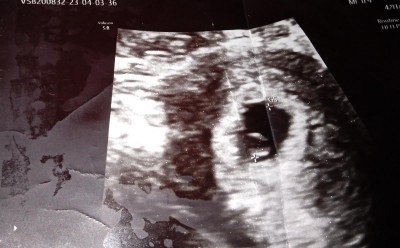

Kizlar yardım sizce bebek tekmi çift mi gözüküyor

Kizlar sizce çoğul gebelik mi anlayamadim bende

Tek duruyor canım hayırlısı

Tek gebelik ama yolk sac var bebek gorunmiyor gordun mu kslp atisi felan

6 haftalık dedi 10 gün sonra gel kalp atışını dinle teyim dedi bebek yok derken içime şüphe düştü

Yanındaki bebeğin beslenme kesesi tek gebelik

Bir tane kese var ama zaten olsa doktor sôylerdi